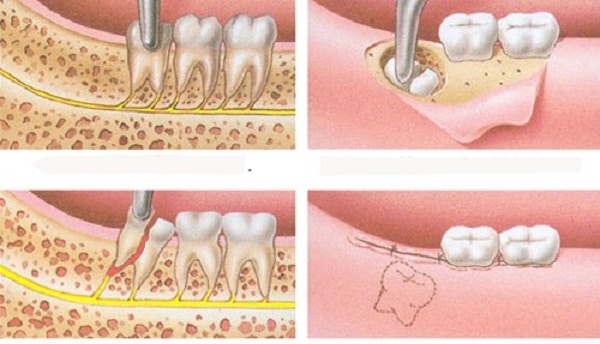

4. NHỔ RĂNG KHÔN (TIỂU PHẪU)

Trực tiếp Bác sĩ Cảnh thực hiện. Kỹ thuật gây tê hiện đại, nhổ răng không đau, xử lý nhanh gọn các ca răng khôn mọc lệch, mọc ngầm.